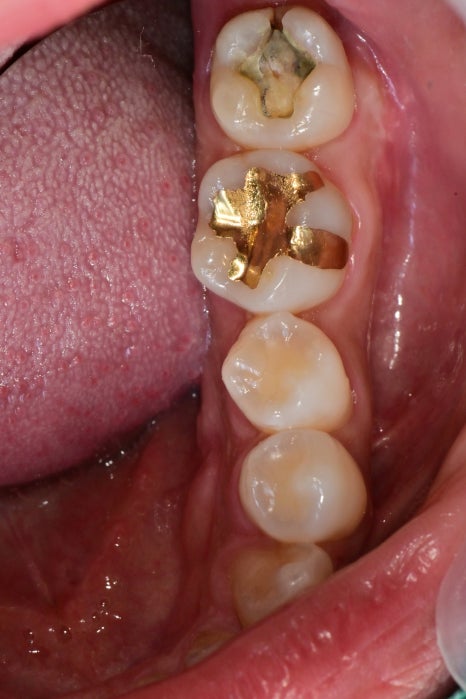

예전에 떼운곳이 떨어졌어요

좌측 아래 맨 끝 어금니의 수복물이 떨어져 있습니다.

치아의 맨 끝부분이 깨져나가있으며

이미 크랙이 진행되어 있지만 증상 자체가 심하지 않기에 신경치료하고 증상을 지켜보기로 했습니다.